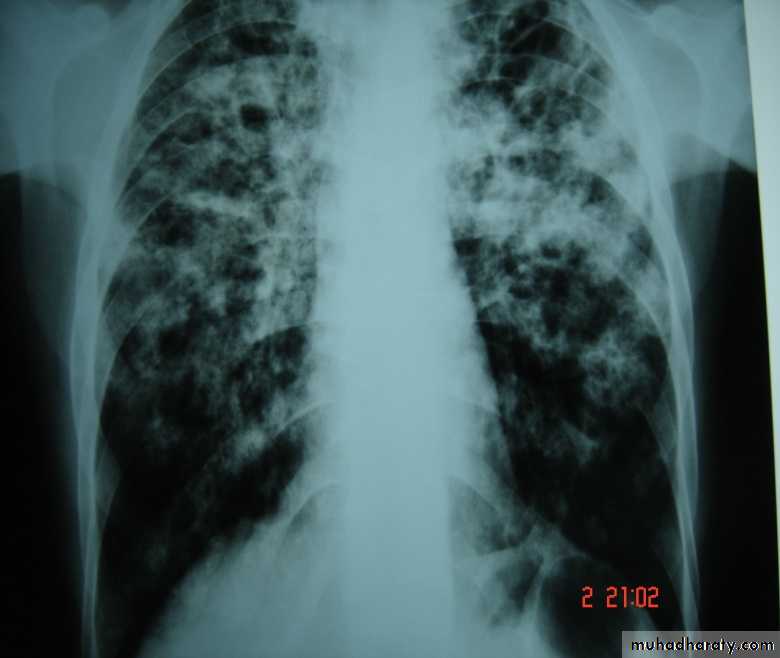

• Pulmonary Tuberculosis:

• Microbiology: Mycobacterium tuberculosis bacilli (acid fast bacilli). As few as 3 organisms can produce infection.

• Clinical Picture: cough (dry mostly), fever, night sweating, loss of weight, loss of appetite, & sometimes haemoptysis.

• X-ray appearance: T.B. could present with any X-ray appearance.(pneumothorax, pleural eff.,

• Collapse, Empyema, miliary shadows, tented diaphragm, thickened pleura, calcified fissures, etc).

• But an apical cavity is the classical & most common appearance.

• Diagnosis: C/F, CXR, Elevated ESR, anemia , Sputum for AFB( 3 morning samples)( Non sensitive), PCR for T.B.( theoretically 100% sensitive).